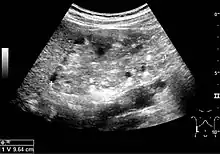

Three methods of scanning can detect angiomyolipomas: ultrasound, computed tomography (CT), and magnetic resonance imaging (MRI).[5] Ultrasound is standard and is particularly sensitive to the fat in angiomyolipomas, but less so to the solid components. However, accurate measurements are hard to make with ultrasound, particularly if the angiomyolipoma is near the surface of the kidney (grade III).[4] CT is very detailed and fast, and allows accurate measurement. However, it exposes the patient to radiation and the dangers that a contrast dye used to aid the scanning may itself harm the kidneys. MRI is safer than CT, but many patients (particularly those with the learning difficulties or behavioural problems found in tuberous sclerosis) require sedation or general anaesthesia, and the scan cannot be performed quickly.[3] Some other kidney tumours contain fat, so the presence of fat is not diagnostic. Distinguishing a fat-poor angiomyolipoma from a renal cell carcinoma (RCC) can be difficult.[6] Both minimal fat AMLs and 80% of the clear-cell type of RCCs display signal drop on an out-of-phase MRI sequence compared to in-phase.[7] Thus, a lesion growing at greater than 5 mm per year may warrant a biopsy for diagnosis.[3]